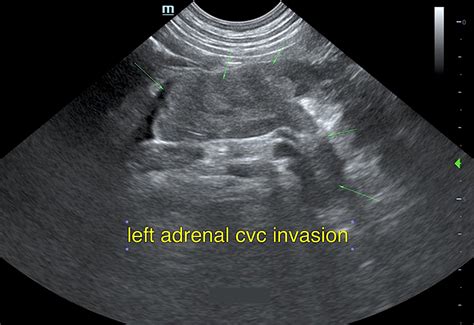

• Imaging tests: Computed tomography (CT) scans and magnetic resonance imaging (MRI) are commonly used to detect adrenal adenomas. These tests provide detailed images of the adrenal glands and can help determine the size and location of the tumor.